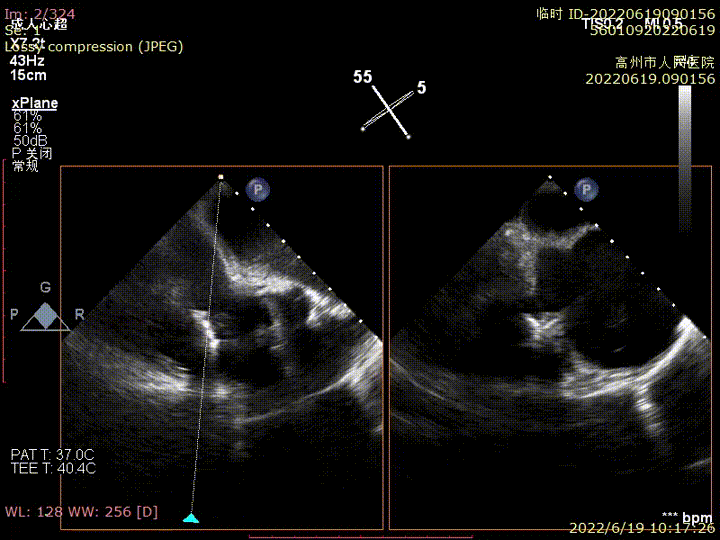

术前TEE提示三尖瓣极重度反流

食管中段RV inflow-outflow引导前叶及隔叶分别捕获